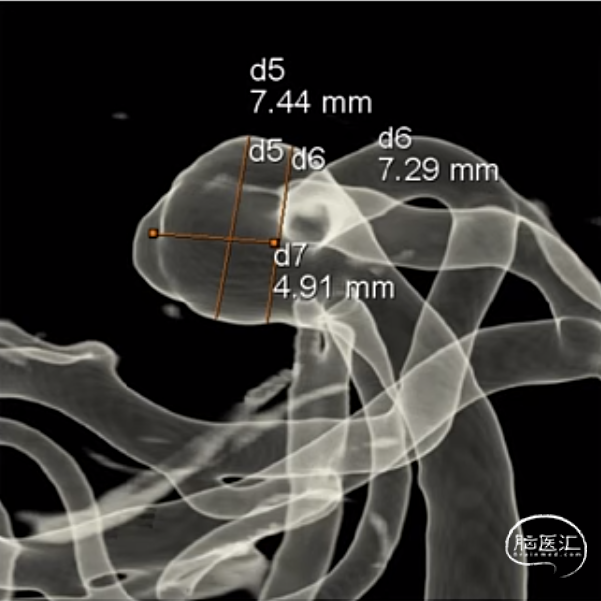

经测量可得动脉瘤宽度平均值为7.0mm,动脉瘤高度为5.18mm,选用WEB™ SL 8*4。

WEB™经由VIA™微导管送入动脉瘤瘤腔并完全释放。术后即刻造影显示WEB™尺寸合适,贴壁良好,分支等血流通畅。解脱后再次造影,可见动脉瘤瘤腔内有明显造影剂滞留。

术后3个月随访,WEB™完全栓塞,动脉瘤完全闭塞。